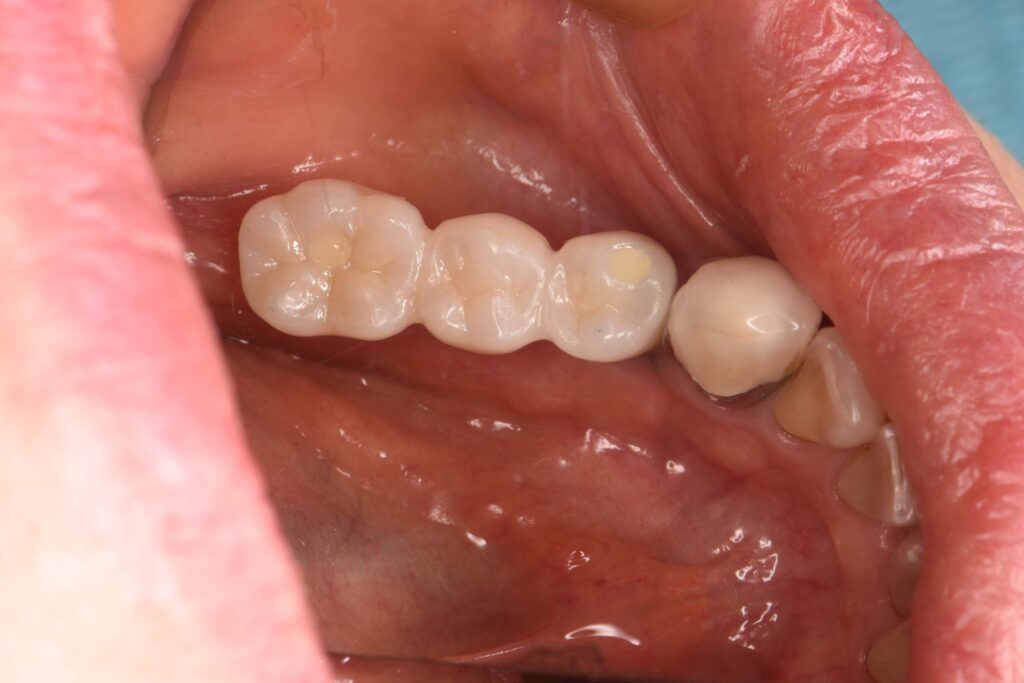

奥歯破折により抜歯後、インプラント治療した症例

After

| 治療内容 | インプラント治療 |

| 治療期間・治療回数 | 2ヶ月半(来院回数は6回) |

| 治療費用 | 528,000円(税込) |

| リスク・副作用 | 外科処置が伴う |

| 備考 | 47歳 女性 |